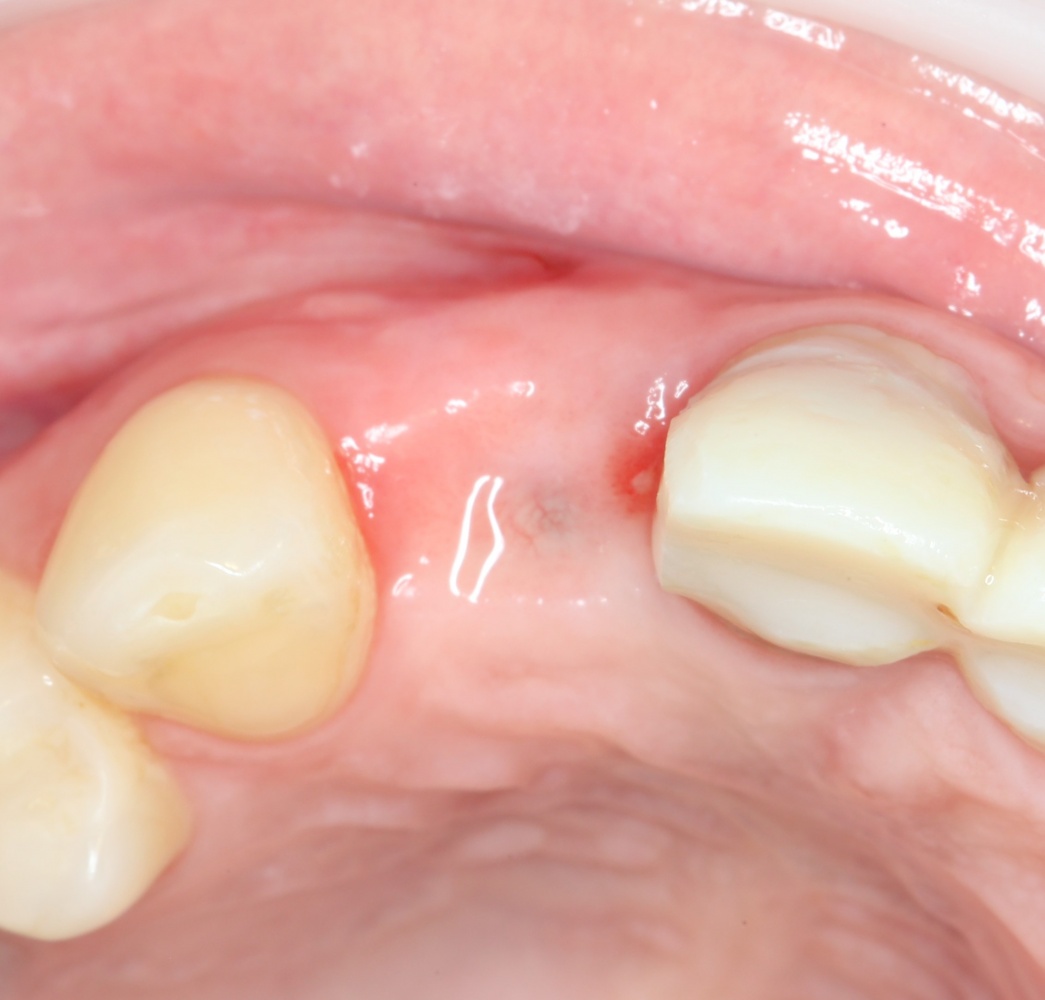

Мы встретились как старые друзья. Честно признаюсь, я очень переживал. Я ожидал увидеть какую-нибудь жуть, утраченную кость, периимплантит, разрушенный вхлам протез и всё такое. Но… всё оказалось не так плохо:

Но фиг с ними, с протезами. Это временные композитные коронки, их не так уж сложно заменить. Меня волнует другой вопрос:

И КЛКТ показала нам, что с имплантатами и окружающей костью всё зашибись. Через 12 лет после операции, отсутствия наблюдения, пофигизма в замене временных коронок! Нужны ли тебе еще какие-нибудь доводы в пользу долгосрочной эффективности метода?